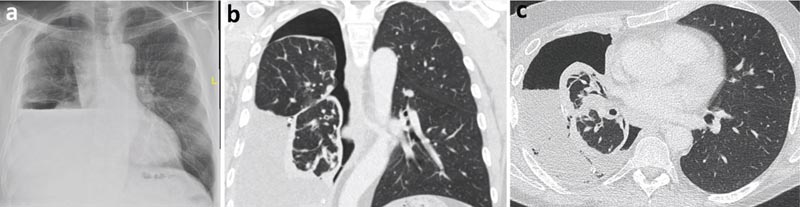

Una radiografia del torace successiva alla toracentesi terapeutica ha rivelato la formazione di idropneumotorace, aumentando la possibilità di un polmone non espandibile. È stata richiesta l’analisi del fluido del versamento pleurico essudativo (proteine 40 g/l e LDH 620 UI).

L’esame citologico ha rivelato un versamento linfocitario senza cellule maligne. La tomografia computerizzata (TC) del torace ha dimostrato una corteccia pleurica parietale che comprende prevalentemente il lobo inferiore destro, probabilmente causando un polmone non espandibile.

Figura 2

a) Radiografia del torace post-toracentesi con idropneumotorace (aria e liquido nella cavità pleurica).

b) TC del torace, vista coronale.

c) TC del torace, vista assiale.